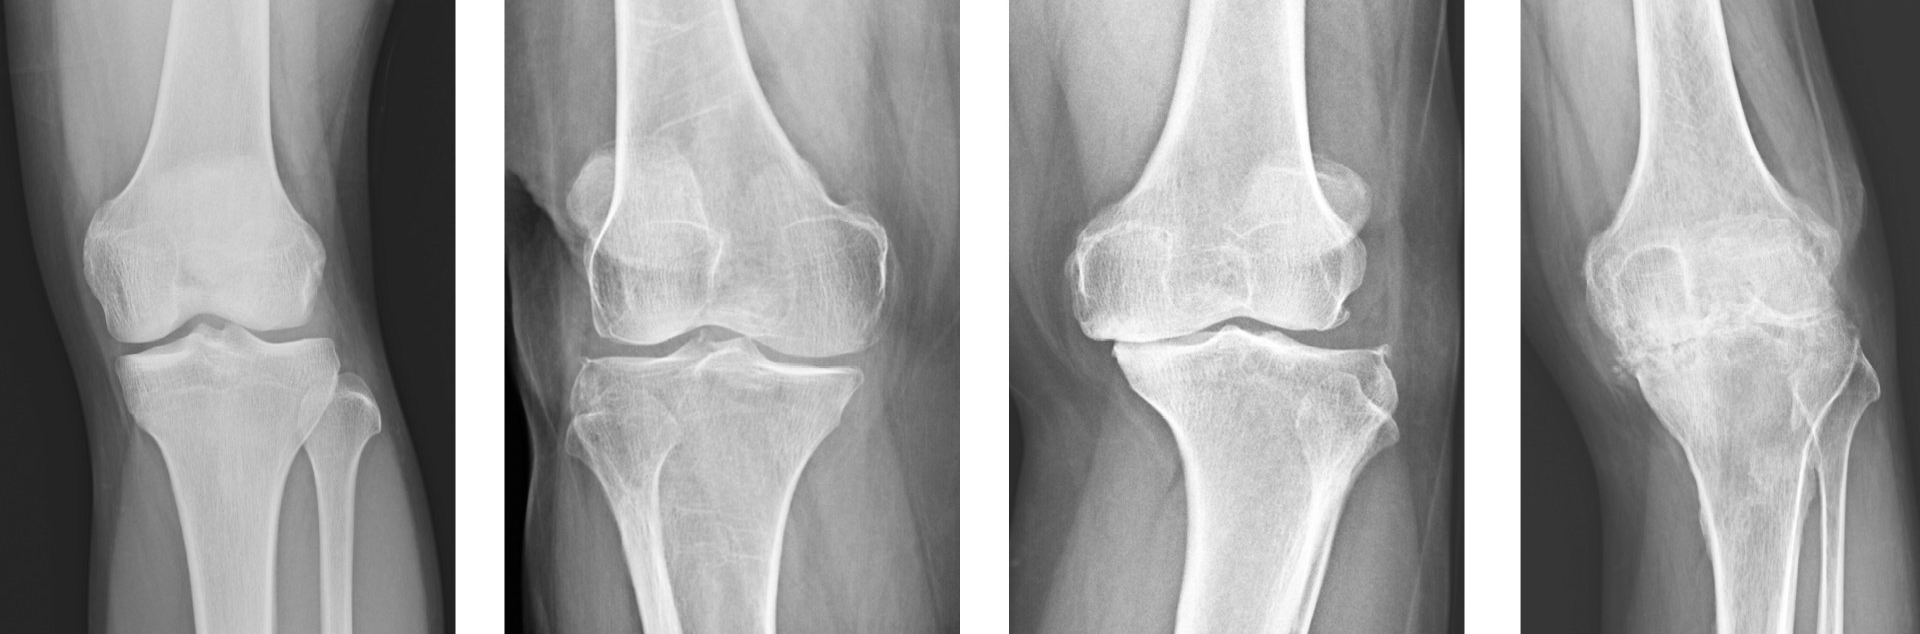

- X-rays are taken to confirm the diagnosis and they should be with the patient weight bearing so as to better detect the degree of joint space narrowing which is one of the key features of arthritis

- MRI scans may also be required, more so in less advanced cases and in younger patients, to better assess location and extent of the arthritis